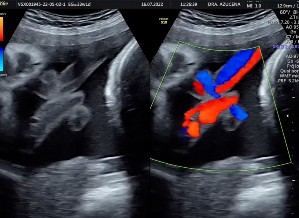

Se evidencia la presencia del signo de la soga colgante. En un corte transversal, se observa al cordón umbilical enrollado sobre sí mismo (Figura 2), formando un lazo y un bucle fijo, con un nudo que configura un lazo en el cordón umbilical, lo que sugiere la posibilidad de un nudo verdadero. Tras la aplicación Doppler color e imágenes 3D, se corroboró la sospecha diagnóstica (Figura 3).

La ecografía en tres y cuatro dimensiones es un método confiable para diagnosticar un nudo verdadero. En un estudio reciente, se reportó la detección de nudo de cordón por un especialista en medicina materno-fetal con una sensibilidad del 87,5 %, especificidad del 99,6 % y precisión del 96,9 %, haciendo énfasis en que la mayoría de los casos se detectaron durante el cribado de segundo trimestre. Es importante mencionar que los diagnósticos incorrectos se han asociado principalmente con la presencia de múltiples bucles de cordón en el tercer trimestre, especialmente cuando se encuentra en una pequeña bolsa de líquido amniótico. Por lo tanto, la presunción diagnóstica de un nudo del cordón de manera prenatal debe tomarse con cautela 5.